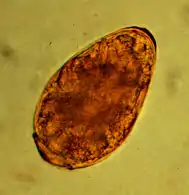

The approximately 85 µm large egg of toxocara mystax in the microscopic image.

The most common roundworm in most cats is toxocara mystax (syn. toxocara cati), infestation with toxascaris leonina is less common. Only in ocelots in Texas was T. leonina detectable in every animal, making it the most common parasite,[2] and in bobcats in Nebraska it was observed almost as often as T. mystax.[3] Both species of roundworm occur worldwide and roundworm infestation is a very common endoparasitosis. The adult roundworms, up to 10 cm long, live in the small intestine. The female worms produce a large number of eggs, which are released into the environment with the feces. The infective larvae develop in the eggs after about four weeks.